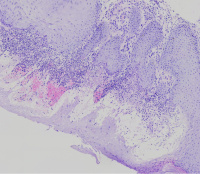

外阴多发赘生物,请教老师们,怎么报告?

性别

女

年龄

62

临床诊断

一般病史

发现外阴数十粒丘疹样结节,伴溃疡

标本名称

外阴丘疹样赘生物

大体所见

灰白色组织两粒0.5*0.3cm

考虑:疱疹病毒感染

疱疹性皮炎。

符合疱疹性皮炎。